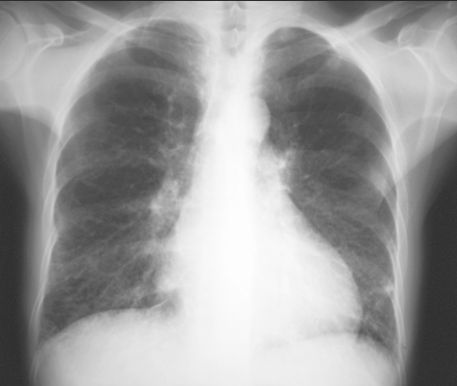

OBRZĘK PŁUC

RTG